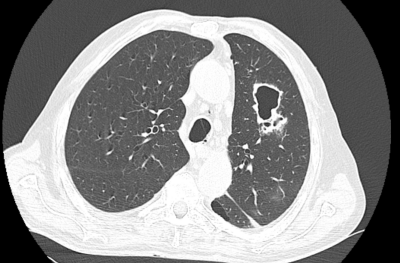

Um exemplo poético com o nome que dei à técnica: nas últimas semanas me deparei com um caso de um paciente internado por insuficiência respiratória e clínica compatível com pneumonia. Sua tomografia mostrava uma grande cavitação pulmonar. Aproveitei um tempinho livre que tinha e pesquisei algum artigo de revisão interessante sobre disgnóstico diferencial de cavitações pulmonares e encontrei esse aqui, da CHEST1. Artigo excelente. E assim, mais uma lacuna (cavidade) foi preenchida.

A imagem da TC de tórax do paciente abaixo. Posteriormente saiu o TRM-TB positivo, confirmando a tuberculose.